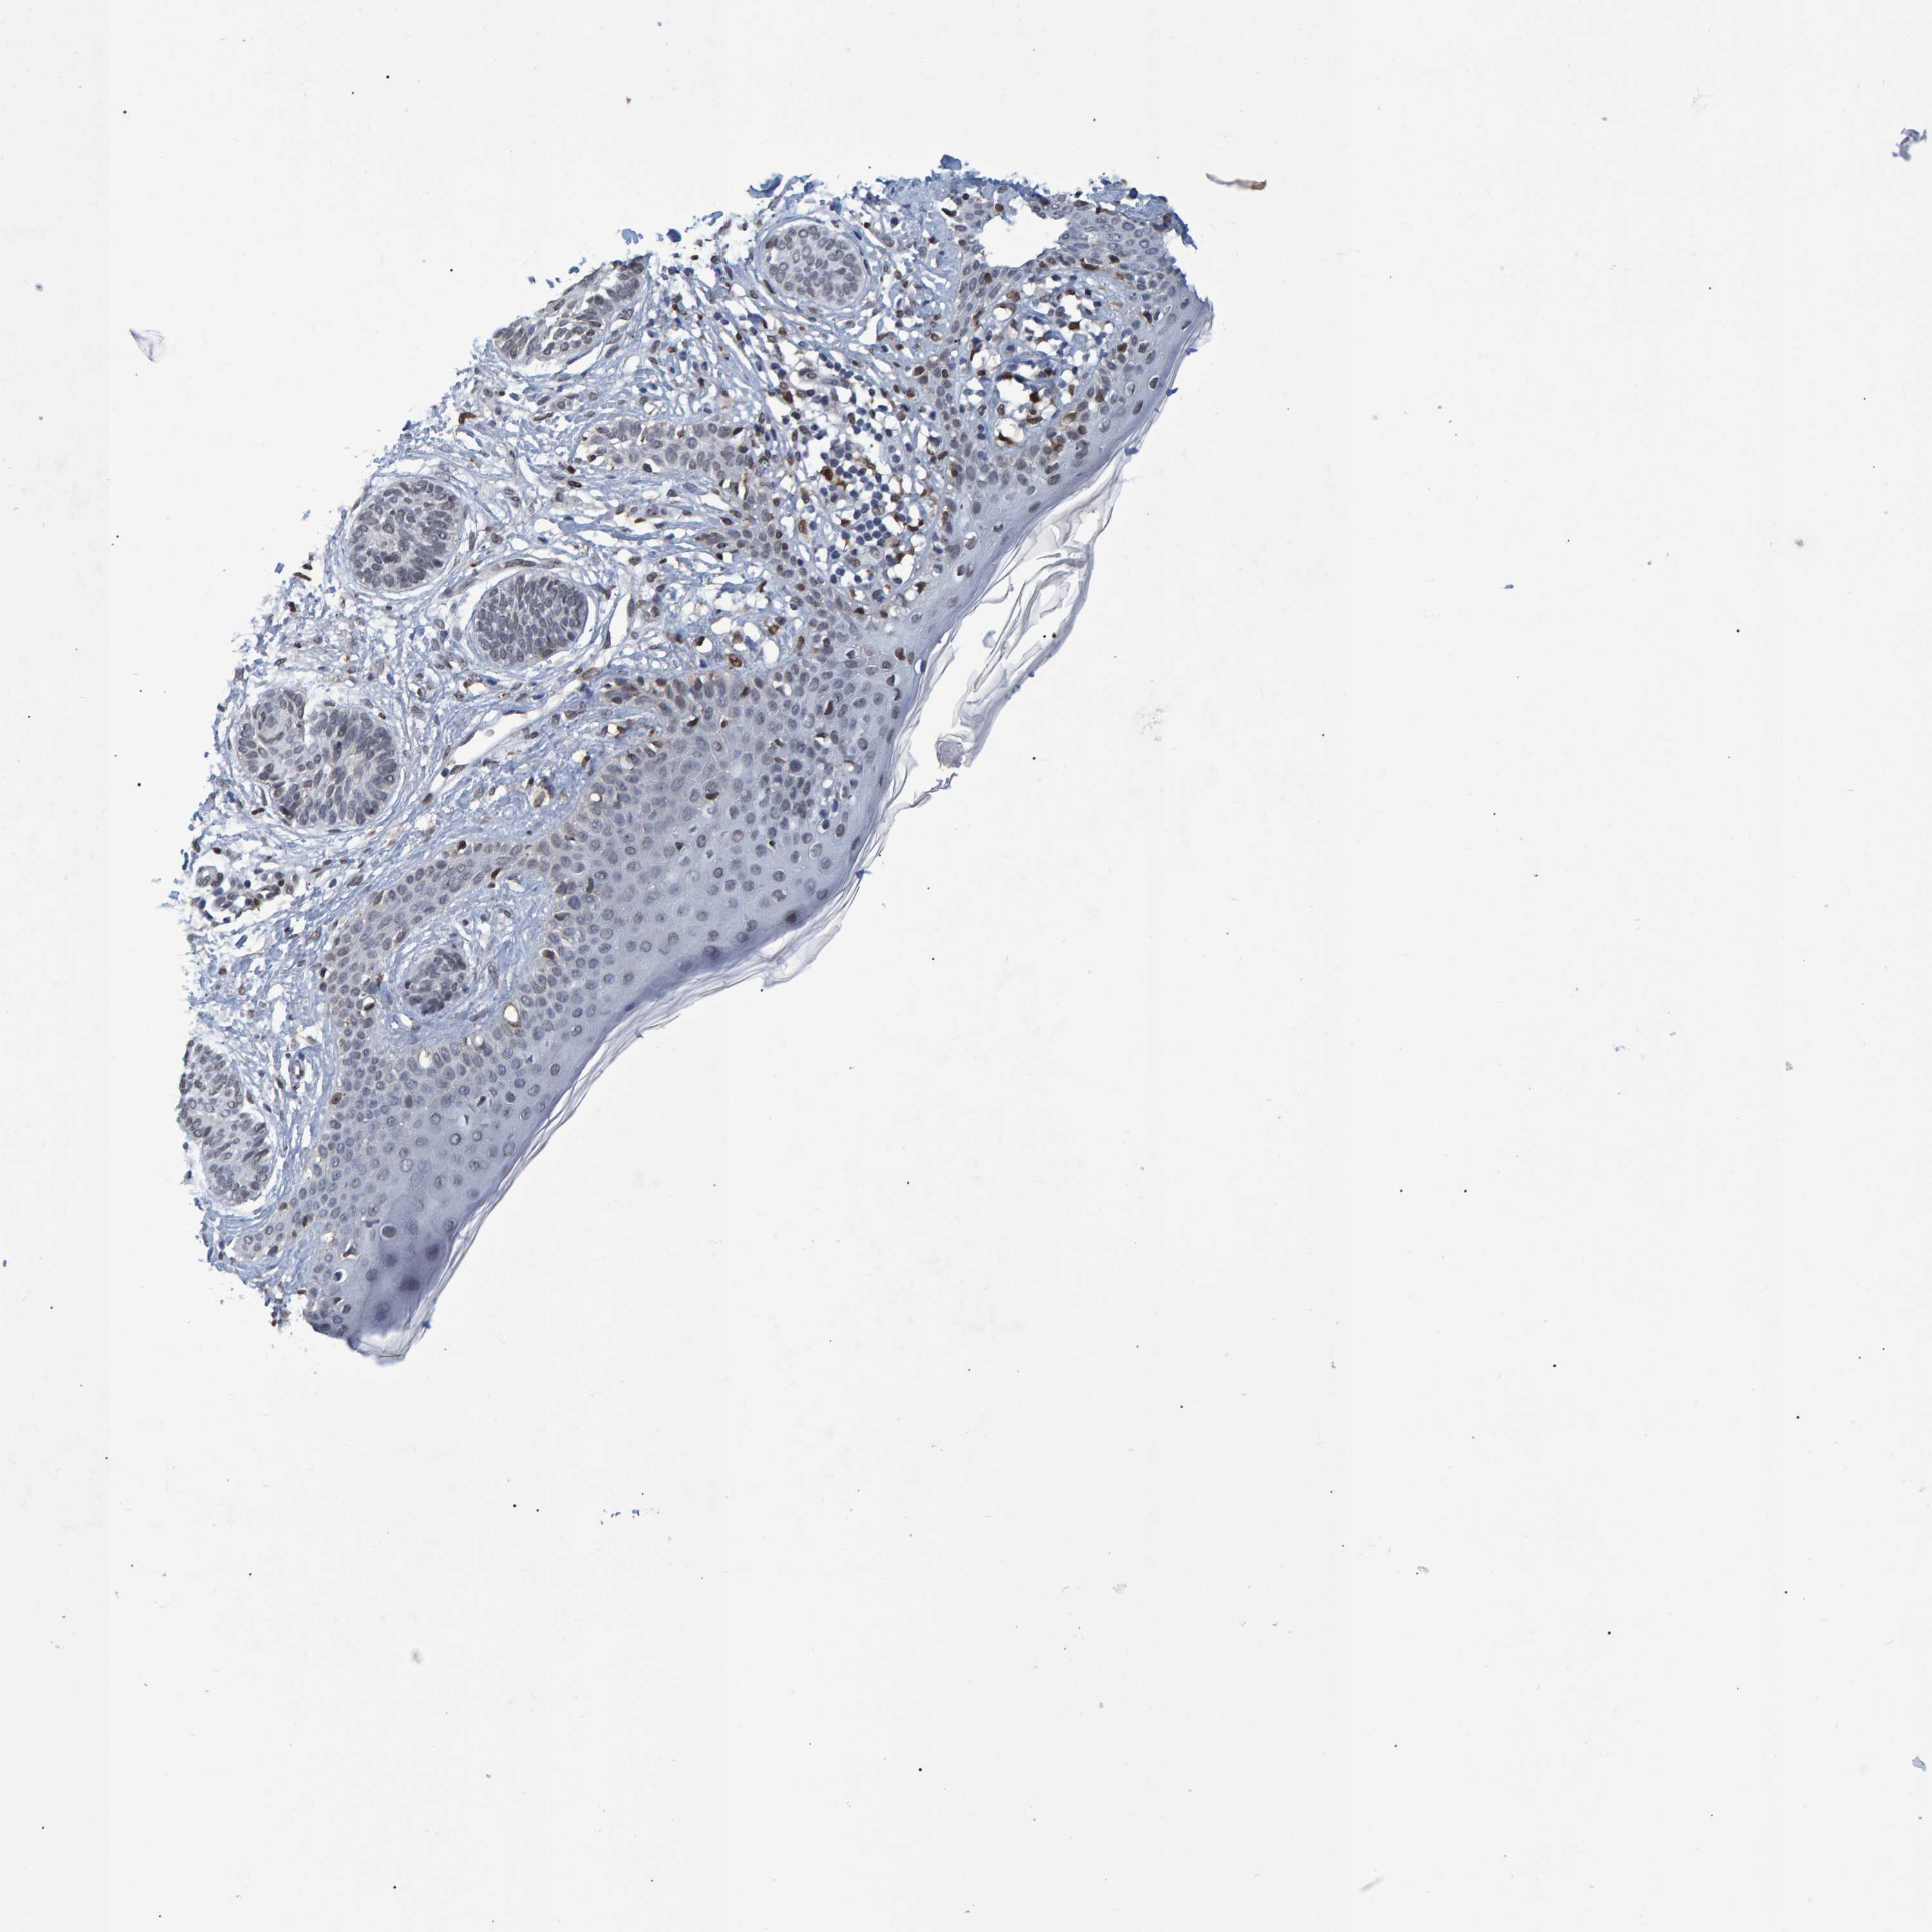

SKIN CANCER - Protein expressioni

A mouse-over function shows sample information and annotation data. Click on an image to view it in a full screen mode. Samples can be filtered based on level of antibody staining by selecting one or several of the following categories: high, medium, low and not detected. The assay and annotation is described here.

Each image is clickable and will lead to virtual microscopy that enables deeper exploration of all samples and also displays staining intensity scores, fraction scores and subcellular localization as well as patient and tissue information for each sample.

Antibody HPA019123

Antibody CAB022602

Staining

High

Medium

Low

Not detected

Intensity

Strong

Moderate

Weak

Negative

Quantity

>75%

75%-25%

<25%

None

Location

Nuclear

Cytoplasmic/membranous

Cytoplasmic/membranous,nuclear

Squamous cell carcinoma in situ, NOS

Squamous cell carcinoma, NOS

Squamous cell carcinoma, metastatic, NOS

Basal cell carcinoma